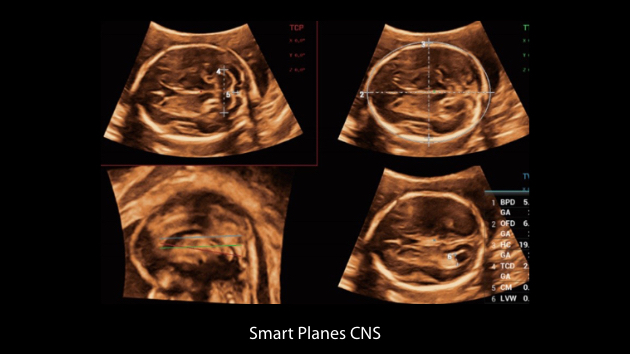

Le Nuewa?I9, con?u spÃĐcialement pour la santÃĐ de la femme et les soins nÃĐonataux, offre une expÃĐrience entiÃĻrement nouvelle gr?ce aux innovations dont il est dotÃĐ, tant à lâintÃĐrieur quâà lâextÃĐrieur. Ces innovations sont dÃĐveloppÃĐes sur la base d'une comprÃĐhension approfondie de scÃĐnarios cliniques complexes, fournissant des rÃĐponses prÃĐcises et adaptÃĐes ainsi qu'une efficacitÃĐ exceptionnelle et une expÃĐrience utilisateur remarquable.

La plate-forme ZST+?est une innovation extraordinaire, reprÃĐsentant une ÃĐvolution de lâimagerie ultrasonore. Elle transforme la formation conventionnelle de faisceaux en un traitement basÃĐ sur les canaux de donnÃĐes. Elle repousse les limites de lâimagerie conventionnelle et du compromis entre rÃĐsolution spatiale, rÃĐsolution temporelle et uniformitÃĐ tissulaire en offrant une qualitÃĐ dâimage exceptionnelle pour des solutions dâimagerie infinies et en constante ÃĐvolution.